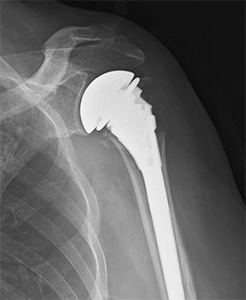

上腕骨近位部骨折(肩の骨折)

高齢者の転倒時に肩や腕を強打して生じることが多い骨折です。

高齢化に伴い、発生数が増加しています。

必要に応じて地域の他病院と連携しながら、もとの日常生活への復帰を目指します。

• 画像:上腕骨近位部骨折

(術前)

(手術例1)

(手術例2)